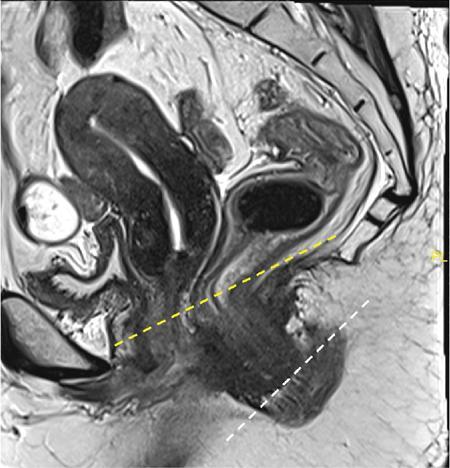

Sumit Mukhopadhyay, Saugata Sen, Aditi Chandra, Argha Chatterjee, Priya Ghosh, Anisha Gehani Cloaca is the part of hindgut caudal to the attachment of the allantoic diverticulum. It divides into a broad anterior urogenital (vesicourethral and urogenital sinus) part and a narrow posterior anorectal compartment/primitive rectum, separated by the urorectal septum. This anorectal compartment gives rise to mid rectum and lower rectum and upper part of anal canal proximal to dentate line. The peritonealized upper part of rectum develops from hindgut proximal to cloaca. The distal most part of anal canal below the dentate line develops from invaginated ectoderm known as proctodeum (Fig. 8.5.1). Initially during development, the rectum is suspended from the posterior abdominal wall by a mesentery, along with the rest of the gut. After completion of rotation of the gut, rectal mesentery fuses with the posterior abdominal wall, majority of rectum becomes retroperitoneal and hindgut mesentery is seen as mesorectum. The artery of the hindgut is inferior mesenteric artery. Anatomically, classically taken as 6 inches (approximately 15 cm), or beginning at the level of S3 vertebra. Surgically defined as 15–18 cm from anal verge (AV), thus anal canal and rectum are considered together for the purpose of surgical and radiological anatomy, though management differs in cases of rectal adenocarcinoma and anal squamous cell carcinoma (SCC). Various trials on rectal cancer neoadjuvant therapy have taken different lengths of cut-off for rectal cancer starting from AV: 9 cm, 12 cm, 15 cm or 16 cm (Table 8.5.1). Rectum continues as sigmoid colon superiorly. The point of transition between rectum and sigmoid colon is controversial. Anatomically, this is the point where sigmoid mesocolon ends, appendices epiploicae are lost and taenia coli gradually converge and disappear. There is no single transition point between these features. These features are not visible to the radiologist/endoscopist as well. Several features defining rectosigmoid junction/transition are variously accepted by different radiologists: Rectum continues as anal canal, which opens to the exterior at AV (mucocutaneous junction). Anorectal junction (ARJ) is considered to be the point at which the angle of the long axis changes, and corresponds to the upper border of puborectalis muscle. The change in axis of anal canal and rectum is well visualized on sagittal MRI. Dentate line lies along the anal crypts (the openings of anal glands), and vertical folds called columns of Morgagni extend superiorly from the dentate line. Anatomists consider the dentate line to be the landmark for ARJ, but the dentate line lies distal to the puborectal sling, and this definition is not clinically relevant. Anal canal is directed posteroinferiorly. At ARJ, the long axis of rectum changes so that it is directed anteroinferiorly. Mid rectum and upper rectum follow the sacral concavity, and the long axis of rectum is again directed posteroinferiorly. Upper rectum is frequently mobile and may not be in midline. Three incomplete folds consisting of mucosa, submucosa and circular muscles, named as Valves of Houston, are seen within the lumen of rectum during endoscopy, but these are not visualized radiologically. The middle valve is roughly at the level of anterior peritoneal reflection, and the superior most valve is at the level of rectosigmoid junction. Surgically and radiologically, rectum is divided into thirds: lower third, middle third and upper third (Table 8.5.2). Most commonly, this division is according to distance or length from AV. Lower third is 0–5 cm, middle third is 5–10 cm, upper third is 10–15 cm from AV (Fig. 8.5.6). Some radiologists define low rectum as 6 cm or less from AV, mid rectum as 7–11 cm and upper rectum as 12–15 cm. The justification of defining low rectum as 6 cm or less from the AV is that, management of most of the tumours at this location suffers from surgical challenges due to tapering of mesorectum and proximity of other pelvic structures. These tumours have a higher rate of CRM positivity, abdomino-perineal resection (APR) and permanent stoma, higher rates of recurrence and mortality, poor function of stoma after sphincter preservation. Another way of defining low rectum, surgical management of which differs from the upper two-thirds, is the portion lying distal to the proximal origin of levators at pelvic side wall. This definition was provided by the English National Low Rectal Cancer Development Programme (LOREC) and is best visualized in the coronal plane by a line joining proximal origins of levators at pelvic side walls (Fig. 8.5.7). ARJ is an important landmark in the management of rectal cancer. Distance between lower border of the tumour and ARJ is important for treatment planning. ARJ is defined as the point at which puborectalis fuses with the levator muscles, and the long axis of rectum changes from anteroinferior to posteroinferior at this point. Its upper extent begins few centimetres above the dentate line, and its length varies from 2–5 cm from AV. Histologically the proximal end of the anal canal is the point at which the columnar epithelium of the rectum becomes the transitional epithelium. Anal canal mucosa has several longitudinal columns, known as anal columns, which end at the dentate line. Below the dentate line the mucosa is smooth and transitions into skin at AV. Approximately at the level of dentate line, the internal anal sphincter (IAS) ends, and the smooth mucosa leads to the intersphincteric plane, distal to which the external anal sphincter extends up to the AV (Fig. 8.5.8). Upper third of rectum is anteriorly covered by peritoneum. Peritoneal covering gradually widens superiorly till it is covered by peritoneum on all sides at the level of sigmoid colon. The exact level of peritoneal reflection varies between individuals, and is quite often seen in axial and sagittal MRI. In axial T2-weighted MRI, a thin hypointense layer with V-shaped attachment to anterior rectal wall is seen representing the anterior peritoneal reflection. This is known as the ‘sea-gull’ sign. Mesorectum and mesorectal fascia (Fig. 8.5.10): lower two-thirds are surrounded by extraperitoneal fat and connective tissue known as mesorectum, which contains lymph nodes, nerves and blood vessels (descending branches of superior rectal artery and corresponding veins). Mesorectal fat is contained within a thin layer of fascia, known as mesorectal fascia (MRF). MRF separates mesorectal fat from extra mesorectal tissues of the pelvis. A relatively avascular plane of areolar tissue lies between MRF and parietal pelvic fascia, facilitating surgery. Importance: Assessment of structures within mesorectum is important for staging and prognostication of rectal cancer. Mesorectal node involvement is N disease. Tumour extension within mesorectal vessels is known as extramural vascular invasion (EMVI) and is thought to be associated with higher chances of vascular dissemination and distant metastases. MRF forms the boundary of the surgical excision plane in total mesorectal excision (TME) – the standard surgery for rectal cancers at present. It is important to understand the various fascial reflections of the pelvis in order to understand pathways of disease spread. The plane between the MRF and the pelvic fascias is the surgical plane. Posteriorly, covering the sacrum, presacral venous plexus and hypogastric nerves, lies the presacral fascia. It fuses with MRF inferiorly at the level of levator ani muscle. The space between presacral fascia and MRF is known as the retrorectal/rectosacral/pelvirectal space, and that between the sacrum and presacral fascia is the presacral space. The presacral fascia continues laterally as the parietal pelvic fascia which covers the lateral pelvic wall. It has two lamellae which encase the pelvic visceral nerves as they course forward from the sacrum to the anterior pelvic organs. The rectosacral fascia/Waldeyer fascia, called as rectosacral ligament by anatomists, is a thickening arising from presacral fascia and running forward to meet the MRF. This divides the rectosacral space into a superior and an inferior compartment, communicating with each other. In males, anteriorly, between the rectum and prostate-seminal vesicles, lies the rectoprostatic fascia/Denonvillier fascia. It is difficult to distinguish from the closely related MRF, and carries the hypogastric nerve and vascular branches to the prostate and male genital organs. In females, anterior to the MRF, lies the rectovaginal septum. According to most views, this septum consists of two layers. The anterior layer corresponds to Denonvillier fascia, and extends from the pelvic floor to the posterior wall of vagina and uterus. The posterior layer is in close relation to the MRF, runs from the pelvic diaphragm and ascends to the peritoneal reflection before fusing with the rectal wall. The lateral rectal ligaments are controversial structures as they are not visualized by imaging and may not carry important structures such as nerves and vessels. However, in some cases, the middle rectal artery may run through them and the accompanying lymphatics may provide a pathway between mesorectal and extra mesorectal lymph nodes. In females, the pelvic floor may be considered to have three compartments, anterior compartment containing bladder and urethra, middle compartment containing the vagina and the posterior compartment containing the rectum. These compartments are supported by the endopelvic fascia and levator ani muscle. The levator ani has several compartments, of which the two most important ones are the iliococcygeus and puborectalis. The iliococcygeus starts as the same fibres as the EAS, and then fans out as a sheet to insert at the pelvic sidewall at the tendinous arch. Posteriorly these fibres fuse in the midline to form the levator plate/raphe. The pubococcygeus and puborectalis are considered together as pubovisceralis muscle. It inserts lateral to the symphysis pubis anteriorly, and forms a sling around the rectum, pulling it anteriorly. Components of the levator ani can be identified in T2-weighted MR images. In males, there are two compartments, anterior containing bladder, urethra, prostate and seminal vesicles and the posterior compartment containing the rectum. Pubococcygeus consists of pubourethralis and puborectalis in males. In sagittal images, the pubococcygeal line is an important reference line, drawn from the inferior border of symphysis pubis to the last joint of the coccyx, representing the level of pelvic floor. The H line is drawn from the inferior aspect of the symphysis pubis to the posterior wall of the rectum at the level of ARJ. This represents the anteroposterior width of the levator hiatus, and upper limit of normal is 5 cm. The M line is the vertical descent of the levator hiatus, drawn as a perpendicular line dropped from the pubococcygeal line to the posteriormost aspect of the H line, and should measure maximum 2 cm. The angle of the levator plate and the pubococcygeal line is also measured. In axial images, the entire normal levator is of uniform thickness and homogeneous low signal intensity. Coronal images show intact iliococcygeus muscle which is convex upwards. The upper half of the anal canal proximal to the pectinate line, the IAS, the conjoint longitudinal coat and the rectum drain lymph upwards into the mesorectal nodes (Fig. 8.5.11) and then lymphatics follow the superior rectal artery into the inferior mesenteric group of lymph nodes. The lymph from these nodes is carried by the intestinal lymph trunk(s). Anal canal below the dentate line along with the EAS drains to the superficial inguinal nodes. Lymphatic vessels also travel with the median sacral artery and drain the puborectalis muscle before finally joining the internal iliac lymph nodes. The internal iliac lymph nodes drain into pre-aortic and paraaortic (lumbar) lymph nodes and efferents from the nodes form the lumbar trunks. The intestinal trunks and the lumbar trunks enter the abdominal confluence of the lymph trunks at the level of the L1–L2 vertebrae, called the cisterna chyli, and then ascend as the thoracic duct. The pelvic lymph nodes lying outside the mesorectum are termed as ‘extra mesorectal lymph nodes’. Above the dentate line: blood supply is from the superior rectal artery, which originates from the inferior mesenteric artery, a branch of abdominal aorta. Superior rectal artery passes in the sigmoid mesocolon and divides into two branches behind the rectum at the level of S3 sacral segment. The superior rectal artery ends in the anal columns by forming a rich vascular plexus/anastomosis with the branches of inferior rectal artery. Blood returns via the superior rectal veins into the inferior mesenteric vein, which drains into the splenic vein and eventually into the portal venous system. Below the dentate line, the inferior anal canal obtains its blood supply from the inferior rectal artery, which is a branch of internal pudendal artery, originating from the anterior division of internal iliac artery. Blood returns via the inferior rectal vein, which drains into internal pudendal veins, internal iliac veins and ultimately into the inferior vena cava (systemic circulation). Thus anal canal is a site of portosystemic anastomosis. Due to the venous anastomoses that occur in the anal canal and the backup of blood flow into the rectal veins, haemorrhoids may be present in patients with portal hypertension. A small part of muscular wall of rectum and anal canal is also supplied by median sacral artery, a direct branch of abdominal aorta arising at the bifurcation of aorta. Nerve supply: The inferior hypogastric plexus lies laterally on the surface of MRF on both sides. It receives sympathetic nerve fibres from the superior hypogastric nerves and parasympathetic ‘nervi erigentes’ from the laterally situated sacral nerves (S2–S4). Laterally, inferior rectal branches of the pudendal nerves and internal pudendal arteries cross the ischio-anal fossa to supply the external sphincter and anal mucosa. T2-weighted small FOV images reveal the layers of rectal wall and details of perirectal soft tissue and pelvic floor most accurately. For adequate assessment of the integrity and involvement of different layers, axial images are needed, which should be obtained perpendicular to the axis of the rectum in that segment. Angle of acquisition should be altered according to the change in axis of rectum (Fig. 8.5.12). The layers of rectal wall from inside to outside are (Fig. 8.5.10): When examining the anorectum with a radial scanning echoendoscope, the internal and EASs can be seen as two distinct rings. The inner hypoechoic ring of tissue represents the IAS the outer hyperechoic tissue ring represents the EAS. The thickness of normal IAS is 2–3 mm, and for EAS: 7–9 mm. The IAS becomes thicker and more hyperechoic with age, while the EAS tends to become thinner with age. Endoscopically, rectum begins at the dentate line and extends to 15–20 cm from the AV. The normal five-layer appearance of rectal wall in EUS is as follows: Imaging in the rectum and anal canal region is mainly for staging of tumours. The most common neoplasm of this region is rectal cancer and preoperative imaging evaluation is required not only for staging early and advanced disease but also for assessing response to treatment and for surgical planning. The techniques described here will mainly pertain to rectal and anal neoplasms. Plain radiographs have a limited role in the evaluation of rectal neoplasms. Primarily, it may be used as a modality in the emergency setting when patients come with constricting colorectal strictures causing large bowel obstruction. Radiographs of the abdomen in supine and erect positions are performed to look for features of bowel obstruction, air-fluid levels and free air under the domes of diaphragm in case of perforation, respectively. Conventional luminal contrast study is now obsolete for diagnosis of tumours in the rectum and anal canal and have been replaced by cross-sectional imaging. Sinogram studies with diluted iodinated contrast have been performed to detect extent of rectal fistulae. Endorectal Ultrasound (ERUS) can differentiate between the layers of the rectal wall and helps detect and stage tumours within the different layers of the rectum. ERUS can view the rectal mucosa in 360 degrees. The layers visualized include rectal mucosa, muscularis mucosa, submucosa, muscularis propria and area between the muscularis propria and perirectal fat. The role of ERUS in rectum is primarily in staging and in posttreatment surveillance of rectal adenocarcinoma. Staging of early tumours requires an ERUS due to its superior diagnostic performance for differentiating T1 from T2 tumours in comparison to other cross-sectional imaging modalities like MRI. As far as surveillance is concerned, endoscopy is mandated as it can detect early asymptomatic recurrences which improves overall survival (OS). This is substantiated by multiple recent meta-analyses in literature. Hence, even for patients on ‘watchful waiting’ as a treatment option after chemoradiotherapy, it is imperative to perform a DRE, EUS, CEA and correlate the findings with restaging MRI. The various recommendations for postoperative surveillance for rectal cancer using endoscopy are enumerated in Table 8.5.3. ASCO: American society of clinical oncology; ESMO: European society for medical oncology; NCCN: National comprehensive cancer network; USMSTF: United States Multi-Society Task Force. Drawbacks include heterogeneity in operator skill and operator dependency as well as inability to pass stenosing lesions. Poor depth of penetration of the probe results in reduced visualization of the mesorectal fat, limited assessment of pelvic side walls and EMVI and reduced diagnostic accuracy for asserting involvement of CRM. Multidetector CT (MDCT) is the primary imaging modality used for rapid evaluation of not only bowel pathologies (luminal or mural) but also for evaluation of surrounding structures such as vessels, lymph nodes and mesentery. The ability to obtain high-quality clinical images through multiplanar reconstructions make it one of the most robust examinations for the initial evaluation of most bowel related pathologies. A routine abdominal CT scan would include acquiring a noncontrast axial image, followed by a portal phase image (at 70–90 seconds). However, for more detailed evaluation of solid organs, a general imaging dataset would include an unenhanced CT, followed by arterial phase (20–30 seconds), portal venous phase (70–90 seconds) and a delayed phase at 3 minutes. Many centres around the world omit the noncontrast scan to reduce radiation exposure. Lesions such as large tumours, pelvic nodes, collections and diverticulosis can be detected by contrast-enhanced CT. CT provides a more holistic evaluation and demonstrates possible complications of tumours such as obstruction, transition point and perforation that may not be clinically evident. However, accurate detection and staging of tumours in the rectum is better performed by MRI. Like TRUS, MRI can depict the layers of the rectal wall with high resolution, especially when performed at 3 Tesla and with an endorectal coil. Although use of endorectal coils may provide improved diagnostic accuracy for T stage as compared with phased-array coils alone, it is known that endorectal coils increase patient discomfort and may account for increasing motion artifacts. Insertion of such coils is also not possible in case of stricturous lesions. Performance of high-resolution imaging using phased-array MRI coils at 1.5 or 3 Tesla, as was used in multicentre trials was excellent. MRI technique and image quality play a critical role in evaluation of rectal cancers, and accuracy is dependent on obtaining high-resolution images that are perpendicular to the plane of the tumour. Particular note is to be made whether the tumour is mucinous or nonmucinous as the former have worse prognosis and higher tendency to metastasize. For technical aspects of MRI, it is recommended by ESGAR that bowels and bladder are emptied. Rectal distension is not indicated as it stretches out the CRM. Minimum slice thickness for such scans is 3 mm. DWI is essential for both primary staging and restaging. Microenemas may be considered to remove air from the rectum and reduce artifacts in DXI sequence. High-risk MRI features for distant metastases include EMVI, mesorectal tumour depth >5 mm, T4 stage, involved circumferential resection margin (CRM). In addition to initial staging prognostic features, MRI also helps in assessing response to neoadjuvant therapy which is also an indicator of survival and chances of recurrence. MRI is sensitive in detecting the presence of lymph nodes but remains nonspecific for differentiation malignant from benign nodes with high diagnostic certainty owing to the presence of micrometastasis even in small-sized nodes (up to 5 mm). Contrast administration is not recommended. Drawbacks of MRI include reduced diagnostic accuracy for identifying early rectal T1 and T2 tumours, and to sometimes differentiate T2 from early T3 lesions. Increased scan times in the elderly and cost may also be constraints in some settings. Virtual colonoscopy can help in identifying primary and synchronous colonic lesions. CT Colonography (CTC) is beneficial after incomplete colonoscopy (due to nonpassable stricture) to evaluate the remainder of the colon. CTC is advocated as a screening test for colonic polyps and colon cancer in vulnerable populations. It has a sensitivity of 93% and a specificity of 97% for detecting polyps >1 cm. MRI scores over all modalities in the local staging of rectal neoplasms. The more common application of PET-CT is in identifying nodal and distant metastases in rectal adenocarcinoma, melanoma and lymphoma. Limitations of PET include poor sensitivity in detecting small (<10 mm) colonic lesions and decreased fluorine-18-2-fluoro-2-deoxy-D-glucose uptake by mucinous tumours. For rectal melanoma, MRI may be performed along with a whole body PET-CT scan for regional and overall staging. Rectal lymphoma does not require local staging and a whole body PET-CT is generally acceptable as the imaging modality of choice. MRI is the imaging modality of choice due to better delineation of the extent and involvement of the anal sphincters. The inguinal nodes are regional nodes in anal cancer and this region is covered in the scan. The most common rectal tumour is rectal cancer. It is also one of the most common malignant neoplasms and the second most frequent cancer occurring in the large bowel. Majority of the patients are in the fifth to seventh decade. However, the incidence of rectal cancer has been on a rise in the younger population. Adenocarcinoma is the commonest histopathologic type of rectal cancer. Other than adenocarcinoma, several other neoplastic lesions also occur in the rectum, but are relatively uncommon (Table 8.5.4). Diagnosis of rectal cancer begins with physical examination/DRE followed by colonoscopy/sigmoidoscopy and biopsy from the mass (see figure below). If malignancy is confirmed on histopathological examination, imaging for staging is ordered (Fig. 8.5.14). MRI is the preferred method for locoregional staging. During staging of early tumours, ERUS also plays an important role. Majority of the guidelines (SAR and ESGAR) accept MRI as the modality of choice for locoregional staging and restaging after neoadjuvant treatment. CT thorax and abdomen is performed for metastatic evaluation. PET-CT is not routinely recommended in metastatic evaluation. ESMO guidelines outline the following indications for PET-CT: (1) If carcino-embryonic antigen (CEA) is high on presentation (2) Extensive EMVI. MRI of the liver may be recommended to evaluate any suspicious or equivocal lesions that are detected on CT scan. Therefore routinely pelvic MRI for locoregional evaluation and CT thorax and abdomen for metastatic evaluation is performed (Table 8.5.5). Based on the investigations, the rectal cancer is staged according to the latest AJCC classification (Table 8.5.6). T0 No evidence of primary tumour Tis Carcinoma in situ T1 Tumour invades submucosa T2 Tumour invades muscularis propria T3 a b c d Tumour invades subserosal tissue and perirectal tissue a <1 mm b 1–5 mm c >5–15 mm d >15 mm T4 a b Tumour invades peritoneum or other organs Tumour penetrates visceral peritoneum Tumour invades other adjacent organs or structures NX Regional lymph nodes cannot be assessed N0 No regional lymph node metastasis N1 a b c Regional lymph node metastasis (1–3 nodes) 1 lymph node 2–3 lymph nodes Tumour deposits in subserosa, mesentery/nonperitonealized perirectal tissues (cannot be differentiated from nodes on imaging) N2 a b Regional lymph node metastasis (>4 nodes) 4–6 node >7 nodes M0 No distant metastasis M1 a B c Distant metastasis Metastasis in one (1) organ Metastasis in more than one organ Metastasis to the peritoneum with/without other organ involvement Once the diagnosis is confirmed and staging investigations are completed, management is usually decided in multidisciplinary team meetings consisting of Surgeon, Radiation oncologist, Medical oncologist, Pathologist and Radiologist. The treatment protocols differ in the United States and Europe (Fig. 8.5.15). The different types of rectal surgeries are enumerated in the Table 8.5.7 and depicted in Fig. 8.5.16. Concept of use of neoadjuvant short course RT, long course RT with chemotherapy and chemotherapy only is a rapidly evolving field. Radiologist should be aware of the protocol used in their institution. A subset of patients (10%–23%) was found to have complete pathological response (pCR) in the postsurgical pathological specimen. There is significant evidence of prediction of pCR on presurgical MRI. Considering the ability of MRI in prediction of pCR, Prof. Habr-Gama and her group suggested the possibility of organ preservation in these patients. Hence ‘watch and wait’ policy came into vogue. In the subgroup where MRI predicts complete response, surgery can be avoided and patients may be followed up every 8–12 weeks using DRE, proctoscopy/sigmoidoscopy and MRI. Both T2W and DWI are used in MRI for prediction of complete response as well as for follow-up for prediction of recurrence. Close follow using the above-mentioned protocol ensures early detection of recurrence and hence treatment. Thus, MRI plays an important role in personalized treatment of rectal cancer. MRI plays an important role in rectal cancer management: During initial staging MRI helps in: In restaging after NACT, MRI helps in: Therefore good-quality high-resolution rectal MRI is required for accurate locoregional staging. Technique and protocol of MRI is summarized in the Tables 8.5.8 and 8.5.9. 1.5T-3.0T magnet strength High resolution T2w sequences Small FOV images Axial and coronal images – parallel and perpendicular to the rectal tumour For low rectal tumours coronal images –perpendicular to the anal canal